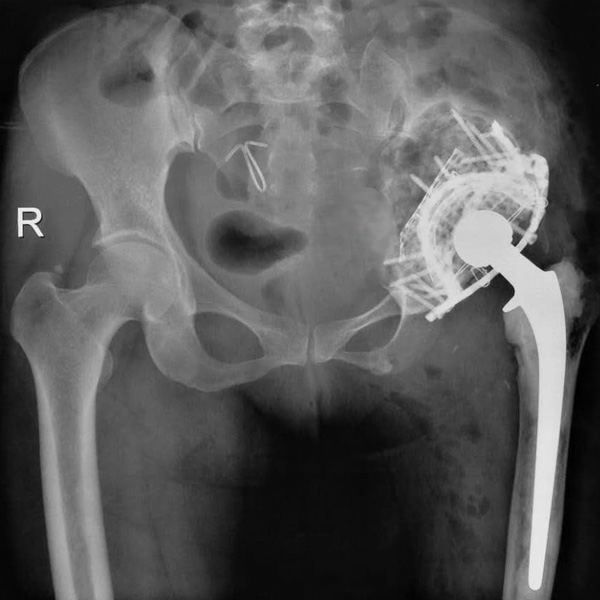

髖關節翻修

患者蘇某,女性,11年前因“左髖關節屈曲攣縮畸形”行左側人工全髖關節置換,近來感覺左髖關節疼痛,不敢行走,經“攜生醫療平臺”就診于哈......